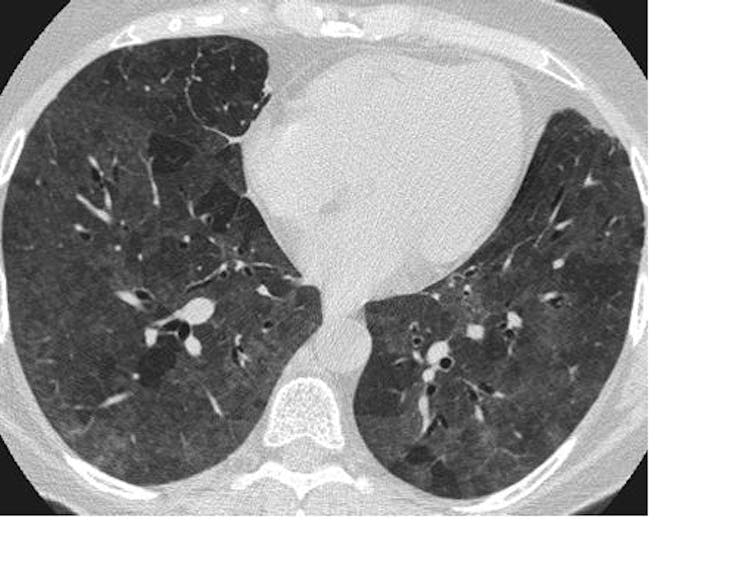

I quickly learned that many patients with advanced COVID-19 disease bore none of the hallmarks of severe respiratory illness until they suddenly collapsed and died. The science behind this early lesson is now emerging, with a study from Wuhan, China, describing pathological lung changes on CT scans of completely asymptomatic patients. Asymptomatic carriage is not uncommon in other virulent infections, such as MRSA and C diff, but what is striking with SARS-CoV-2 (the virus that causes COVID-19) is that it may be accompanied by underlying organ damage.

The researchers found lesions consistent with inflammation of the underlying lung tissue (ground-glass opacities and consolidation, to use the medical jargon), which are not specific to SARS-CoV-2 infection and may be seen in many other forms of lung disease. What remains a mystery is why, despite these changes, patients do not display typical symptoms of pneumonia, such as severe shortness of breath.

Lesions on a CT scan cannot determine what treatment is needed. It still requires a personalised decision based on clinical judgement. So even as scientific understanding grows, I will apply Osler’s advice with renewed conviction: attend to your patient with all five senses at full alert. They will teach you what you need to know.![]()